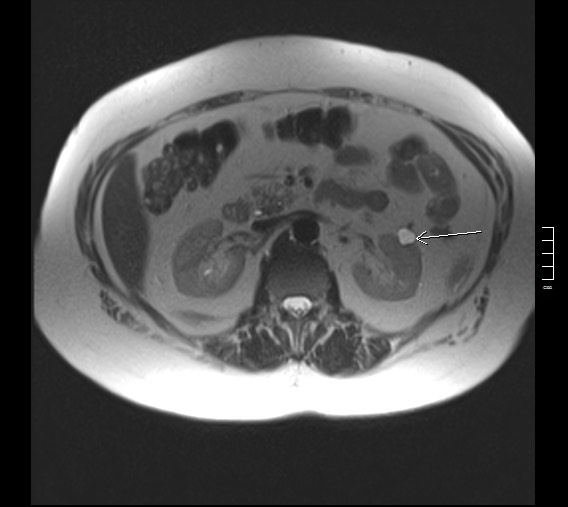

2916. Киста почки, указанная стрелкой, локализуется